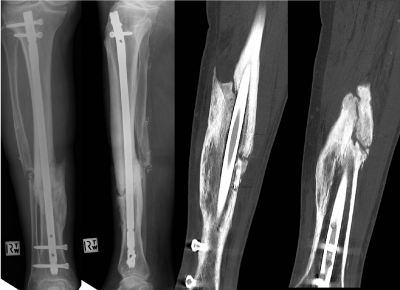

Figure 4: (a) Antero-posterior radiograph and (b) lateral radiograph of the tibial osteotomy fixed with an intramedullary nail at one year postoperatively, (c) and (d) Computed tomography (CT) of the tibial osteotomy fixed with intramedullary nail at 1 year postoperatively. Both image slices indicate that union has not been achieved.